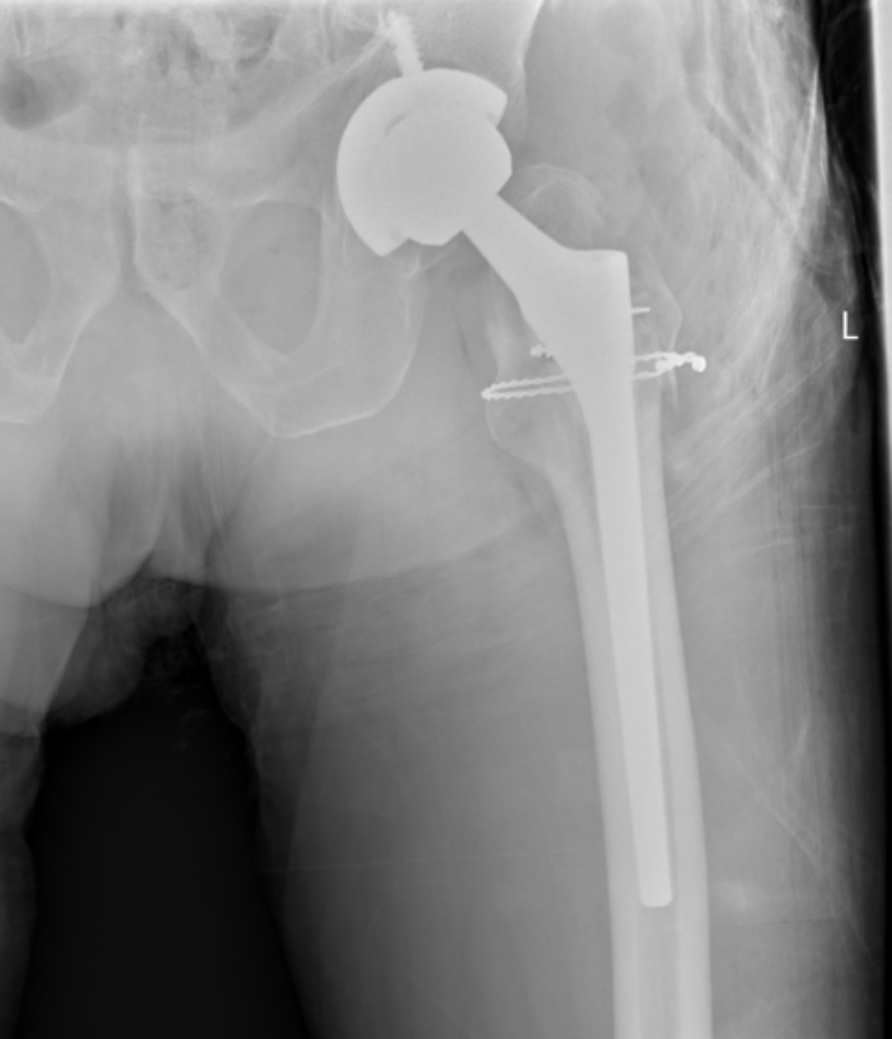

典型病例影像学表现见图1~10。图1为86岁女性右侧股骨转子间骨折(Evans Ⅲ型)患者,术前X线示骨折断端部分错位,术后X线示骨折位置可以及假体位置良好;图2显示了一名81岁男性患者,诊断为左侧股骨转子间骨折,类型为Evans V型,合并股骨干陈旧性骨折。患者接受了生物型加长柄半髋关节置换手术,并进行了股骨近端的钢丝捆扎内固定。术后X线示假体位置良好,股骨近端予钢丝捆扎固定;图3为87岁女性左侧股骨转子间骨折(Evans V型)患者,术后X线示假体位置良好,股骨大小转子骨折位置可,钢丝捆扎固定在位有效;图4为75岁女性左侧股骨转子间骨折(Evans V型)患者,术前X线示左侧股骨转子间骨折PFNA术后、骨折未愈合、内固定断裂。术后假体匹配良好,股骨近端钢丝内固定稳定可靠;图5为75岁男性左侧股骨转子间骨折(Evans IV型)患者,术后股骨大转子出现轻度位移,假体位置正常。图6为87岁男性左侧股骨转子间骨折(Evans V型)患者,给予DAA入路加长柄半髋关节置换,术前X线片,清晰地显示出左侧股骨转子间的骨折情况,术后X线影像,显示股骨的大小转子骨折位置良好,钢丝内固定装置在位稳定,假体位置良好;图7为77岁女性右侧股骨转子间骨折(Evans V型)患者,术前X线片显示右侧股骨转子间存在骨折且股骨大小转子均有累及和移位,术后X线片显示股骨小转子轻度移位,内固定装置位置稳定,假体位置良好;图8为70岁男性左侧股骨转子间骨折(Evans III型)患者,术前的X线片,清晰地显示了左侧股骨转子间的骨折情况,股骨近端髓腔钙化灶,术后假体位置满意;图9为77岁女性右侧股骨转子间骨折(Evans V型)患者,术前X线片,显示右侧股骨转子间及转子下部位骨折情况。术后假体匹配良好;图10为71岁男性右侧股骨颈骨折(Evans IV型)患者,术前X线片,显示右股骨转子间骨折的情况;术后X线表明股骨的大转子和小转子骨折位置保持良好,内固定装置稳固,术后假体位置正常。

(a) (b)

Figure 3. An 87-year-old female patient with left intertrochanteric fracture of the femur (Evans V type). (a) Before surgery; (b) After surgery

3. 87岁女性左侧股骨转子间骨折(Evans V型)患者。(a) 术前;(b) 术后